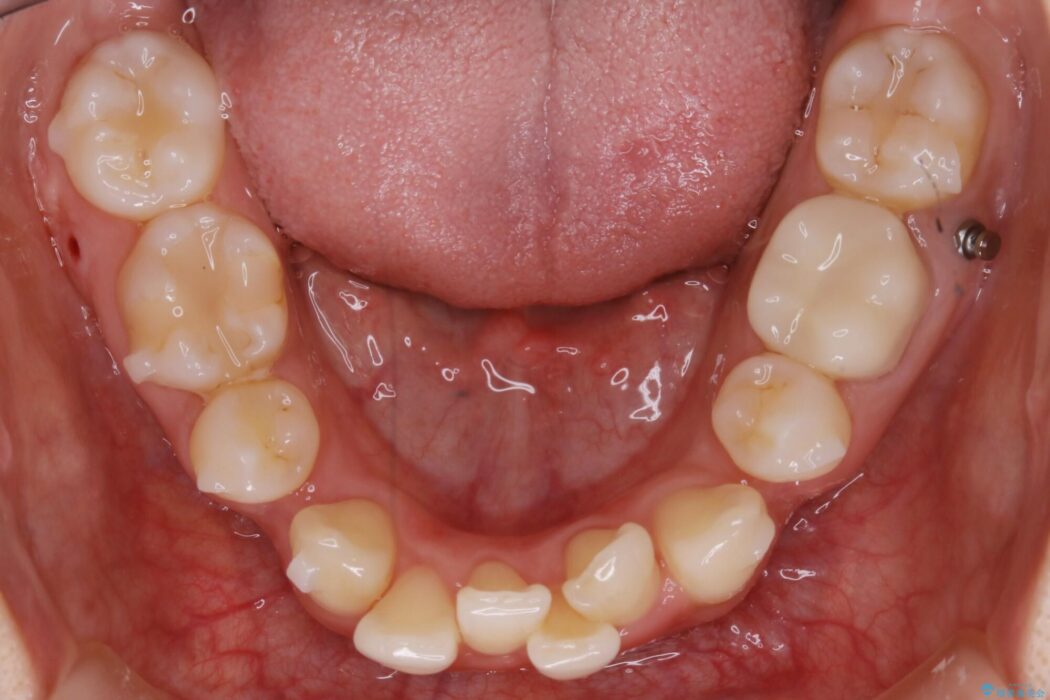

【20代女性】抜歯矯正で叢生をなおす

ガタガタな歯並びをなおしたいとのことで来院されました。

左右の奥歯が前方に寄っていることにより八重歯の発生や重度の叢生に繋がっていました。

加えて患者様の顎の大きさに対する歯の数が多いことが叢生の原因になっていることから、抜歯した上で歯列を整えるほうが最終的な仕上がりとして良い結果になると判断しました。

まず噛み合わせに問題が少ない奥歯の位置を極力変えないように上下左右4番目の歯を抜歯することで歯列矯正のためのスペースを確保し、空いた隙間で前歯の凹凸をきれいに並べていくこととしました。

また、ご要望がありマイクロインプラント治療もしています。